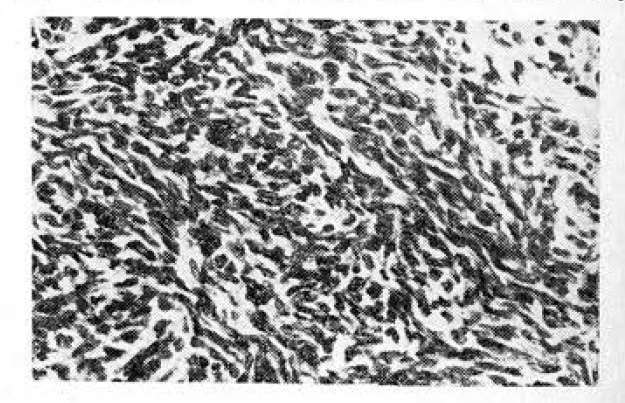

Выраженные изменения выявляются и в семенниках. Стенки семенных канальцев резко утолщаются вследствие усиления склеротических процессов, сопровождающихся выраженным угнетением сперматогенеза (рис 3). У онкологических больных уже в возрасте 30—39 лет в просветах семенных канальцев наблюдаются уменьшение, а часто и полное исчезновение сперматид и сперматозоидов, что, по-видимому, можно объяснить задержкой дальнейшей дифференцировки сперматоцитов. Наряду с этим, особенно при прогрессировании опухоли, происходит угнетение и сравнительно ранних фаз сперматогенеза. В более поздних стадиях опухолевого роста в канальцах остаются лишь сперматогонии и поддерживающие клетки.

Рис. 3. Угнетение сперматогенеза у мужчины 34 лет, больного раком желудка. Окраска гематоксилин-эозином.Х 308.